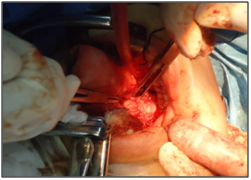

Figure 6  A careful dissection along the path of through Wharton duct shows its intimate relationship with the lingual nerve. The separation of the tongue and floor of the mouth including the lingual nerve, displays the mylohyoid muscle. The previous separation of the posterior margin of mylohyoid allows to visualizes the surface portion of the submandibular gland.

The intra-oral route, requires nasotracheal intubation, after which lidocaine with epinephrine (1: 100,000) is injected into the mucosa to achieve hemostasis. After inserting a probe into the Wharton's duct meatus, an intraoral incision is made through the mucosa of the floor of the mouth, from the meatus behind the lingual side of the retromolar region. A careful dissection along the path through Wharton is duct shows its intimate relationship with the lingual nerve.

The separation of the tongue and floor of the mouth including the lingual nerve, displays the mylohyoid muscle.

The previous separation of the posterior margin of mylohyoid allows to visualize the surface portion of the submandibular gland. Blunt dissection is used to release the submandibular gland of surrounding structures. Applying transcervical submandibular gland pressure on the floor of the mouth helps viewing, and gland is removed carefully and hemostasis is performed. A drain can be inserted through the incision, whereafter the mucosa is reapproximated with an absorbable suture, thus concluding the surgical procedure.